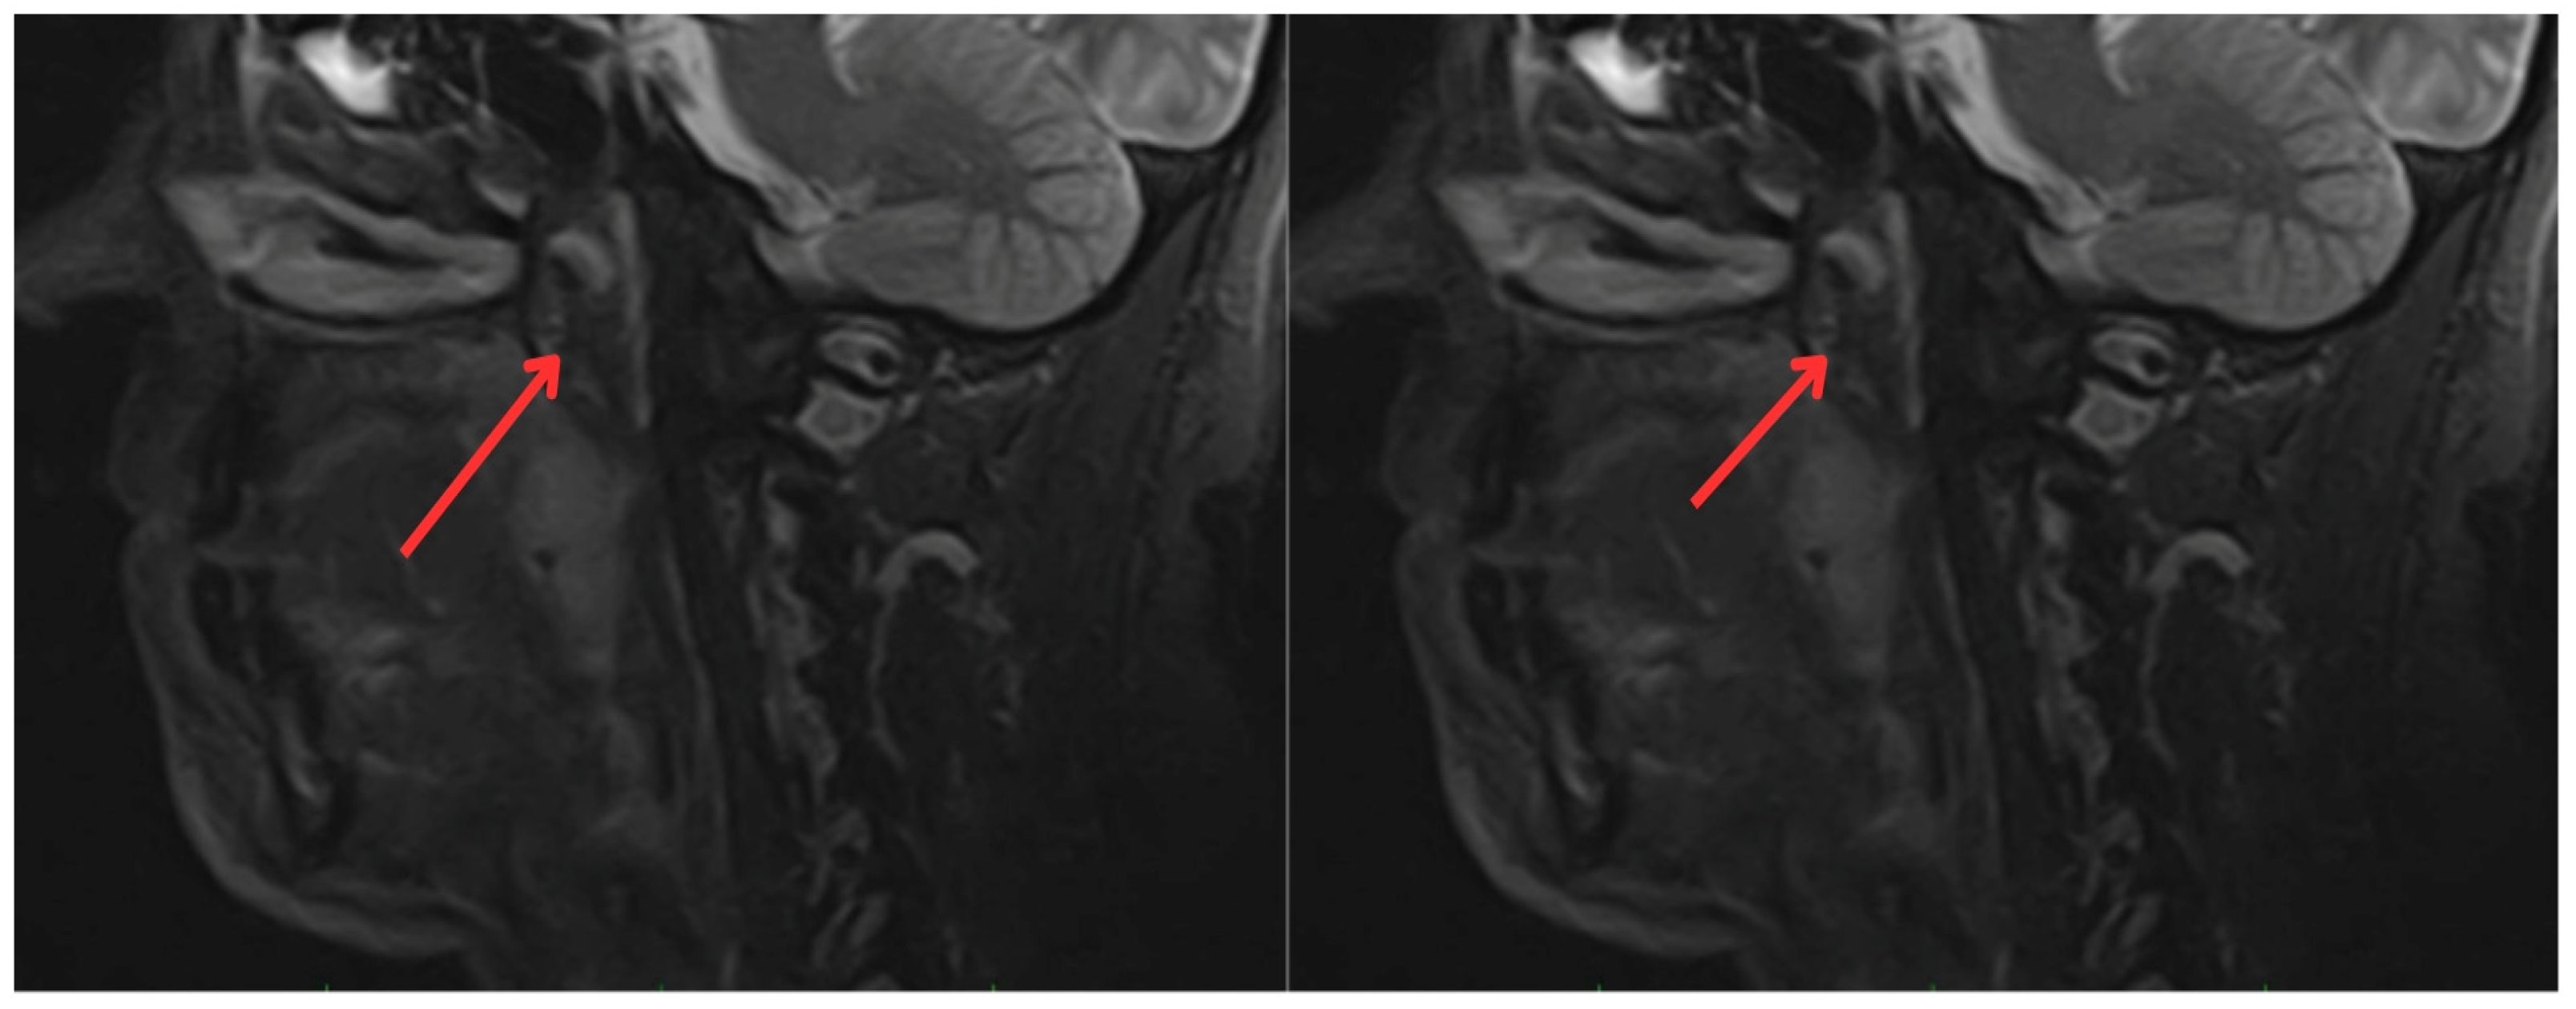

In June 2022, the head and neck surgery service, suspecting a relapse of rhabdomyosarcoma, requested nasopharyngoscopy and magnetic resonance imaging (MRI) of the paranasal sinuses (Figure 2). The reports indicated the presence of a mass with irregular enhancement affecting the mucopharyngeal space and the right palatine tonsil and extending to the tongue base with neoplastic characteristics. This led to an expanded imaging study with a contrast-enhanced neck MRI (Figure 3), which showed irregular enhancement of a mass compromising the mucopharyngeal space and the right palatoglossal arch, measuring 22 × 10 mm, similarly affecting the right palatine tonsil and extending to the tongue base with a neoplastic appearance, as well as lymphadenopathy at the right cervical station three, which was suspicious.

Figure 3.

Contrast-enhanced magnetic resonance imaging of the neck: irregular enhancement, forming a mass that involves the mucopharyngeal space and the right palatine tonsil, extending to the tongue base, with a neoplastic appearance (red arrows).